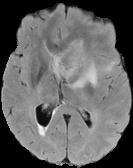

We conducted experiments on four brain imaging datasets: BraTS2017, BraTS2018, BraTS2019, and ISLES2022 [33, 34, 35, 36]. The BraTS datasets, developed for the MICCAI brain tumor segmentation challenge, contain 285, 285, and 335 labeled cases respectively, categorized into high-grade and low-grade gliomas. Each case includes 3D MRI scans from four modalities (T1, T2, FLAIR, T1c); we primarily used FLAIR. Preprocessing involved brain region cropping and intensity normalization. Dataset splits were 200/25/60 as train/val/test for BraTS2017 and BraTS2018, and 250/25/60 for BraTS2019. All experiments were conducted independently with models trained from scratch.

ISLES2022 focuses on stroke lesion segmentation in 3D multimodal MRI, with 250 cases including DWI, ADC, and FLAIR. We used DWI and split the dataset into 150 training, 40 validation, and 60 testing samples.

Quantitative Results. Tables 3–4 report results on BraTS2019, BraTS-2018, BraTS2017, and ISLES2022 datasets with limited labeled data (4% or 10%). On BraTS2019, our method outperformed most competitors in Dice, Jaccard, and 95HD, with a notable lead under the 4% setting, despite slightly lower ASD. On BraTS2018, it consistently surpassed all baselines, achieving nearly 2% higher Dice than the runner-up. It also achieved top performance on all metrics for BraTS2017, highlighting strong robustness and generalization. For ISLES2022 with 10% labeled data, our method significantly outperformed DAE-MT and closely matched the fully supervised model.

Qualitative Results. Figures 4, 3 present visual comparisons of the predicted segmentation results from our method and other baselines on the middle slice of the BraTS2018, BraTS2019, and ISLES2022 datasets. Our method demonstrates greater robustness and better coverage of the ground truth regions, particularly in areas where other methods fail to identify lesions and incorrectly classify them as background. Furthermore, our approach yields more accurate boundaries and preserves the overall shape of the target structures more effectively than competing methods.